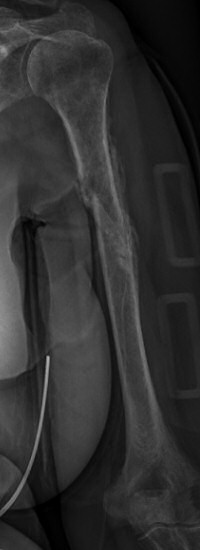

Det finns också t.ex. Holstein-Lewis: spiralfraktur på distala tredjedelen av humerus, i 22 % av fallen påverkas n. radius [3].

Holstein-Lewis-fraktur